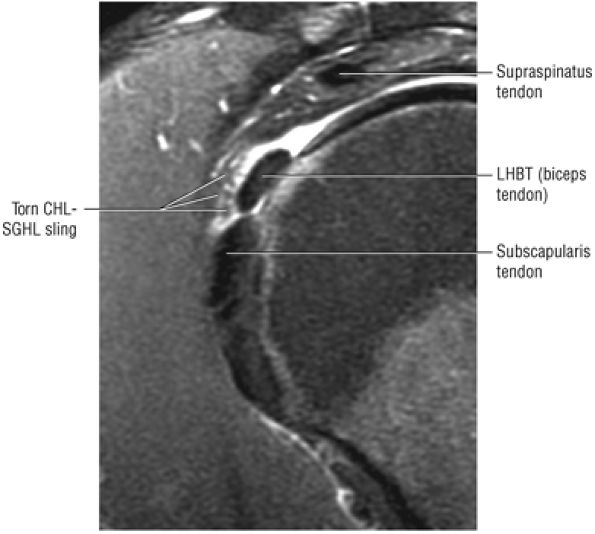

The rotator cuff interval is located between the superior aspect of the subscapularis tendon and the inferior aspect of the supraspinatus tendon. This interval contains the coracohumeral ligament and the SGHL. A hidden lesion of the rotator interval has been attributed to pathology of the CHL–SGHL confluence, which forms the biceps sling or pulley. Surgical closure of the interval appears to eliminate excessive inferior translation.59